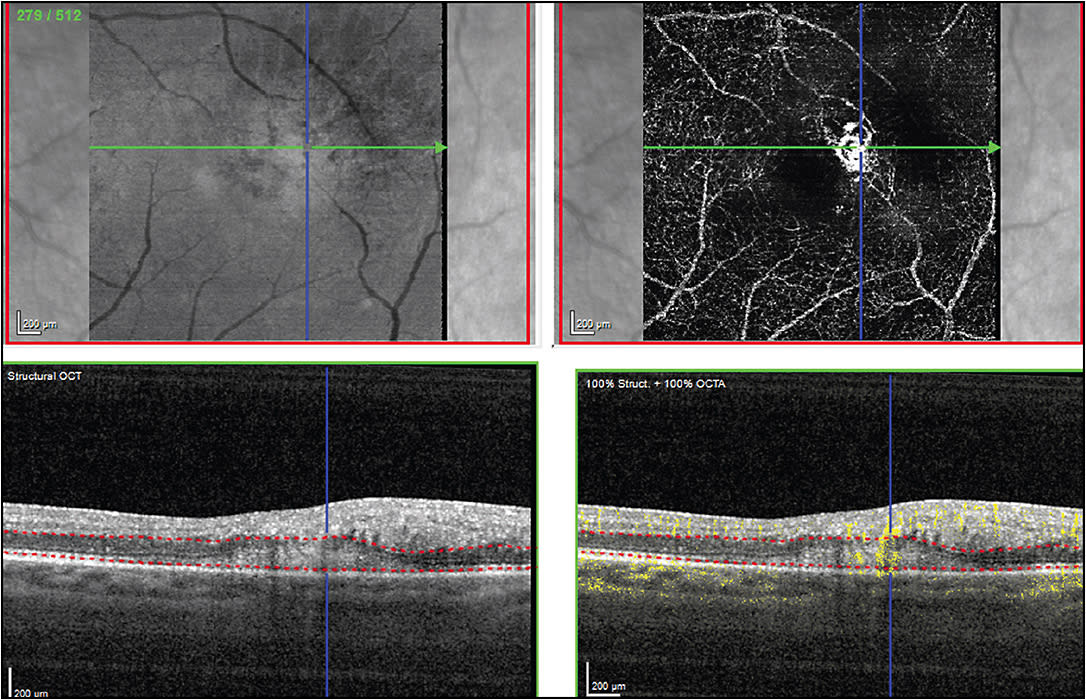

Projection artifact: OCTA is susceptible to an artifact where superficial retinal vessels are seen in deeper retinal structures. With our fellows, this often causes confusion and misdiagnosis of CNVMs that are not actually present. Currently, we examine the superficial layers and compare them to deeper layers to see if there are similar patterns. If so, we ignore those vessels. We also use the OCT B scan with flow overlay to see if superficial vessels are projecting deeper in the retina. The presence of this artifact is challenging, and makes identification of small CNVMs difficult (Figure 3).